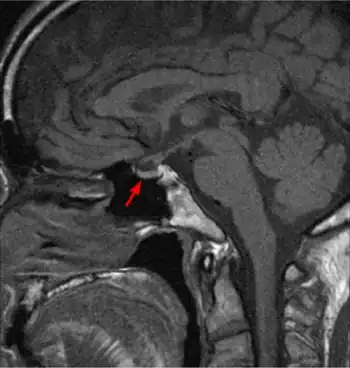

Hyperthyroxinemia is a thyroid disease where the serum levels of thyroxine are higher than expected.[1]